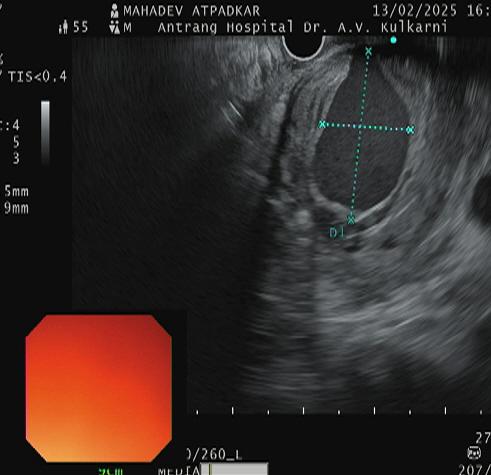

A 53 years- old male presented with a history of repeated GI bleeding for 20days. He had undergone UGI scopy and colonoscopy twice elsewhere with no obvious source of bleed. He was referred to us for further management Initial investigations revealed low haemoglobin levels (3.4), necessitating multiple blood transfusions. CECT abdomen done revealed 4.2×3.4cm pseudo aneurysm arising from Gastro duodenal artery branch within pseudocyst. There was bleeding within pseudocyst. Endoscopic ultrasound (EUS) guided coil +glue was performed to manage the pseudo aneurysm. Post procedure imaging showed Complete Occlusion of the pseudo aneurysm, and the patient was stabilized with supportive care, including IV fluids, antibiotics, and proton pump inhibitors (PPI)

The advantage of EUS guided coiling is, its mininmally invasive, real time and complete occulsion can be seen with help of a doppler.